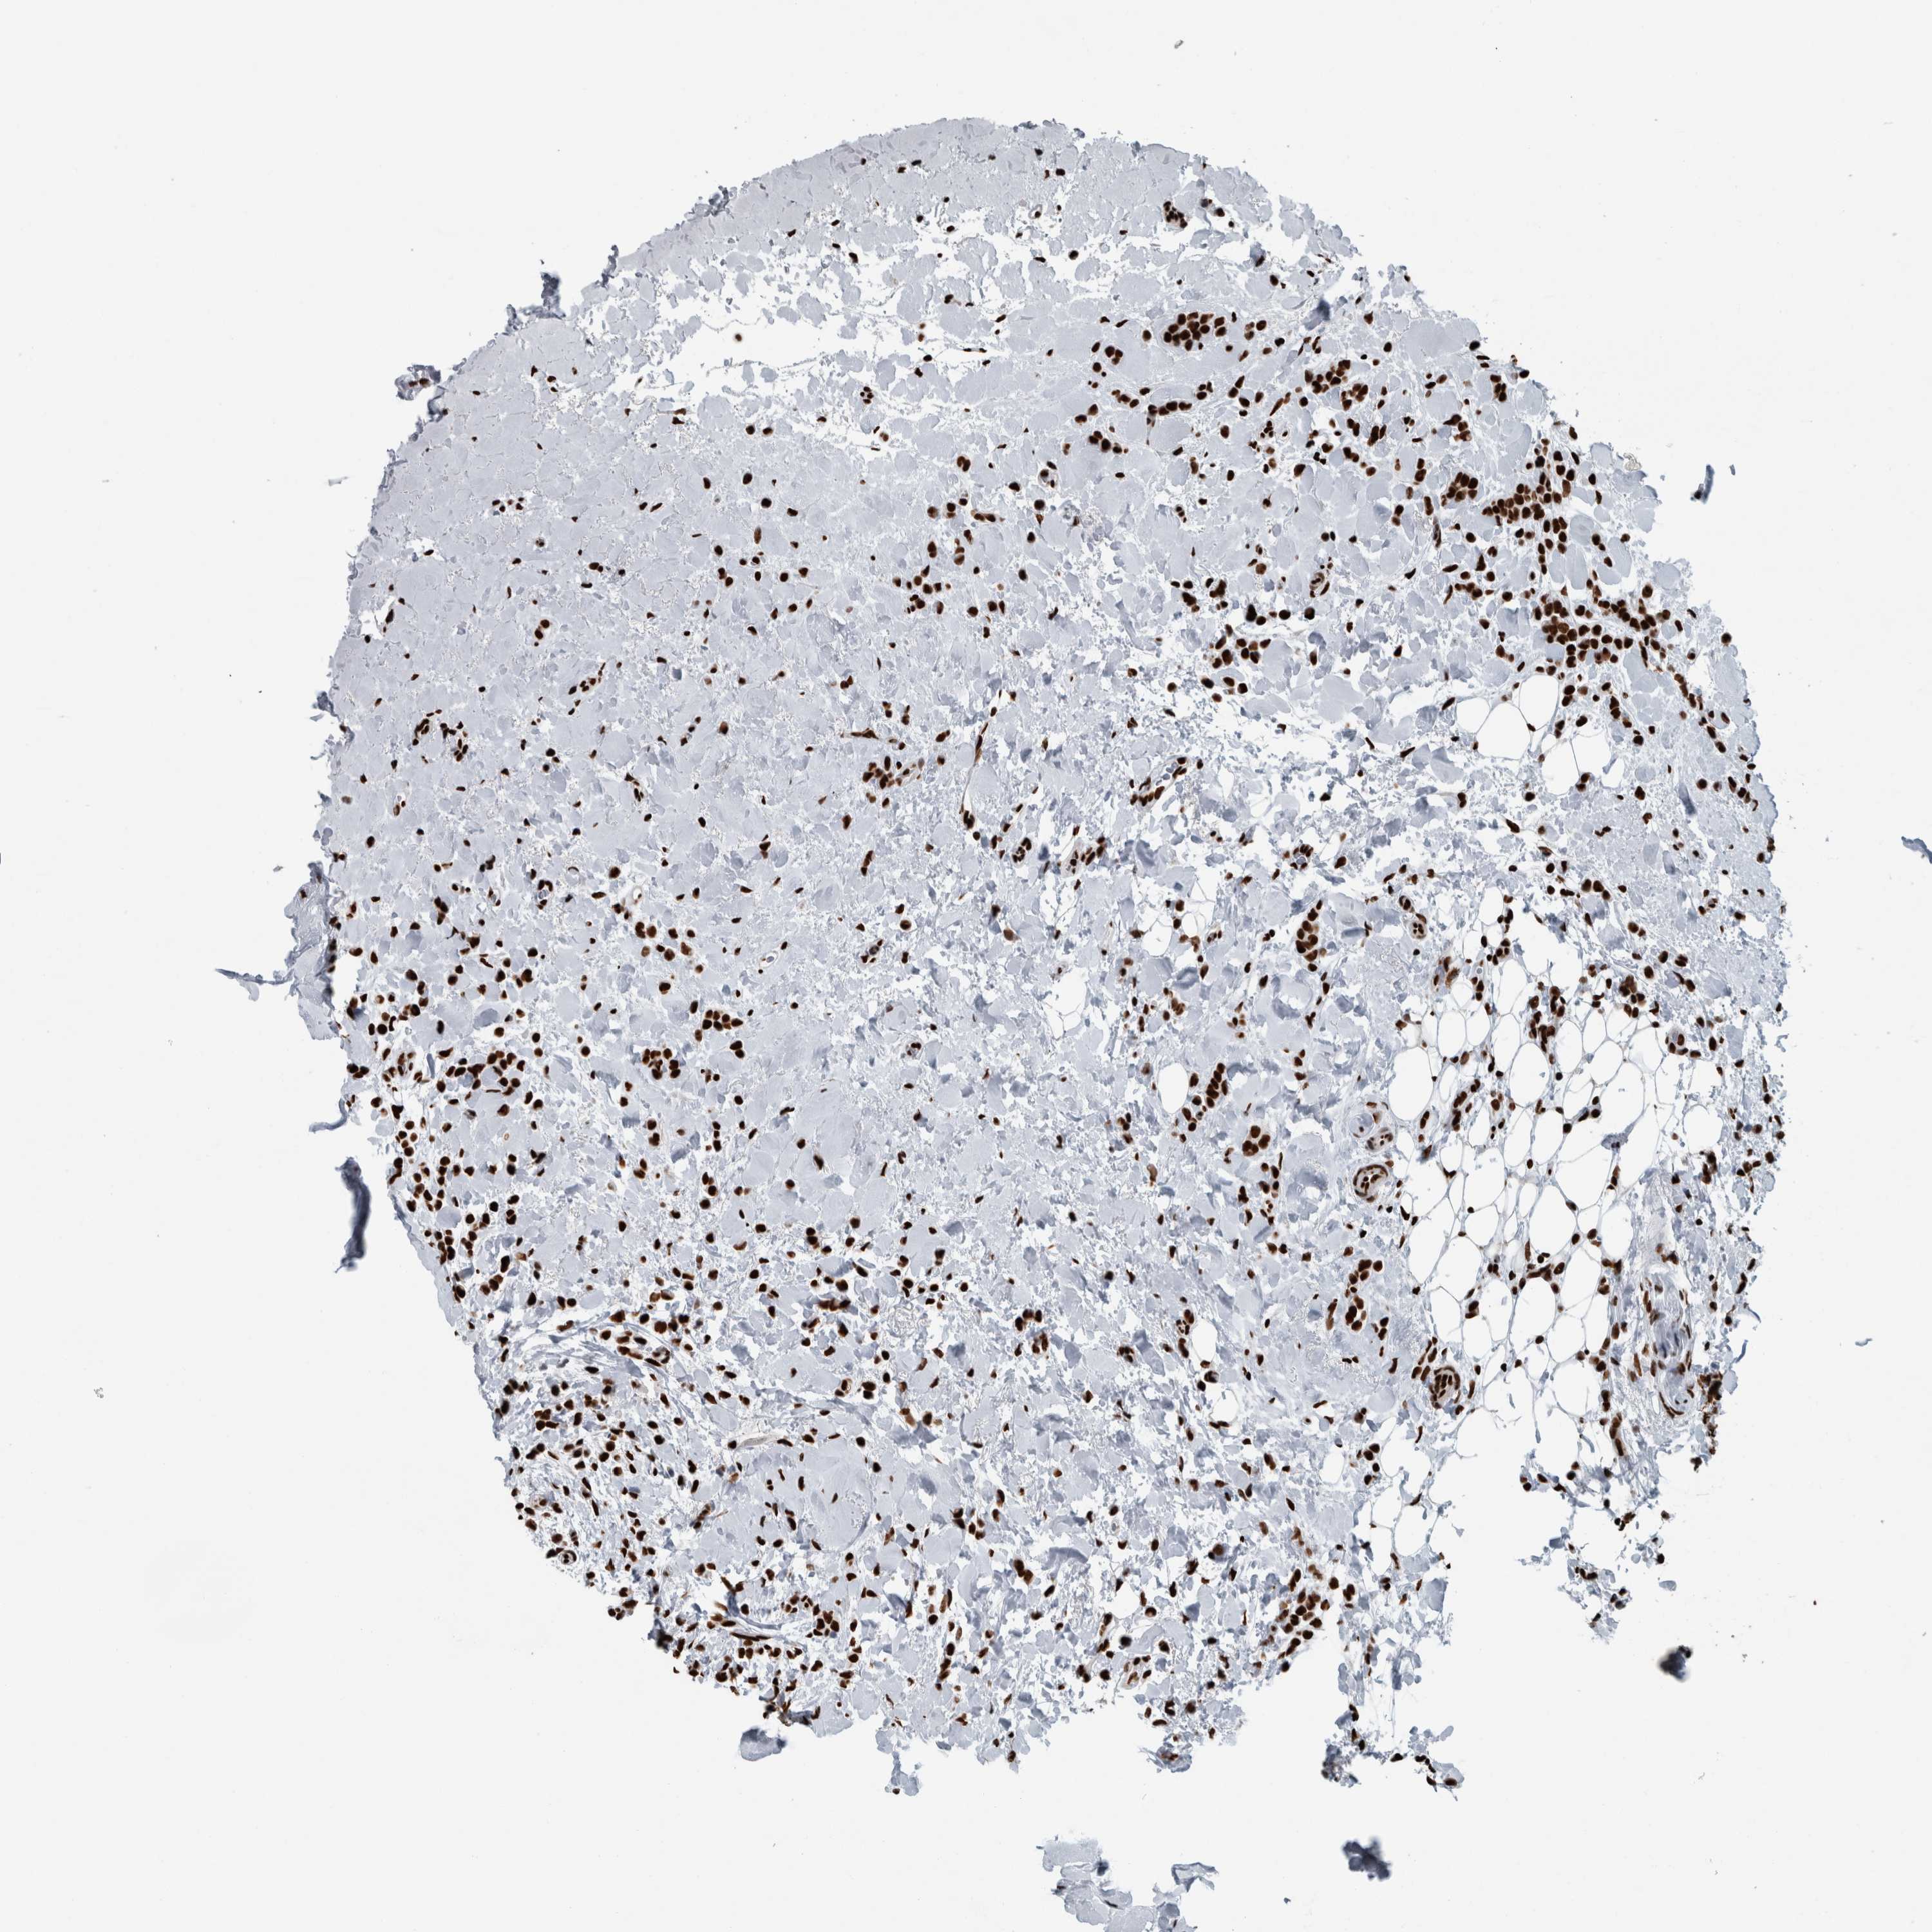

CANCER BREAST CANCER Show tissue menu

BRCA TCGA BRCA VALIDATION PROTEIN EXPRESSION

ANTIBODIES

AND

VALIDATION